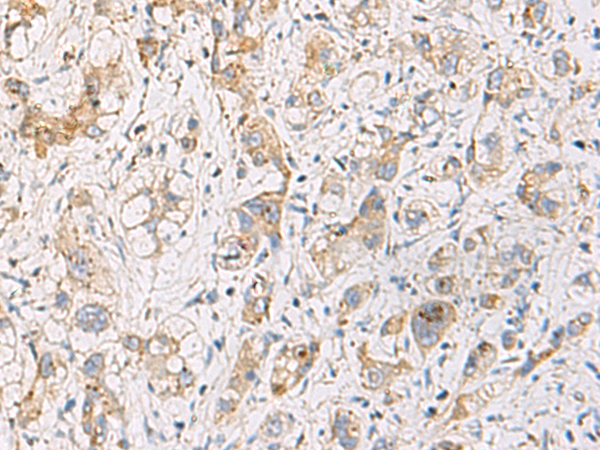

IHC positive control: |

Human liver cancer and Human cervical cancer |

IHC Recommend dilution: |

100-200 |